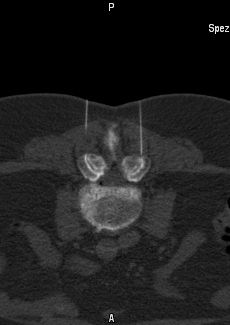

- Thermische Verödung: Dabei werden mit Hilfe des Hochfrequenzstroms die versorgenden Nerven (medialer Ast des Ramus dorsalis N.spinalis) der jeweiligen Gelenken verödet. Die Behandlung findet ambulant und unter Lokalanästhesie (örtlicher Betäubung)mit oder ohne Sedierung statt. Nach CT-gesteuerte Platzierung der Spezialsonden wird zunächst mit Hilfe eines speziellen Verfahrens der Nerv aufgesucht und dann gezielt mit ca. 90°C Temperatur verödet.

Bei der Ausschaltung der Facettengelenke (FAA), der Rippengelenke (CTT, CVT) oder des Iliosakralgelenks durch Nervenverödung werde gezielt Teile des Gelenks und schmerzempfindliche Nerven mit Hilfe von Ethanol (96%iger Alkohol), Hochfrequenz- oder Laserenergie ausgeschaltet. Hierfür wird eine kleine Kanüle präzise am Gelenk oder Nerven platziert, durch die dann das Ethanol, die Lasersonde oder Hochfrequenzelektrode eingebracht werden kann. Der Verlauf der Behandlung wird durch wiederholte CT- oder Kernspinkontrolle überwacht. Nach der Gelenkausschaltung bleiben die Patienten etwa eine Stunde zur Beobachtung im Institut.